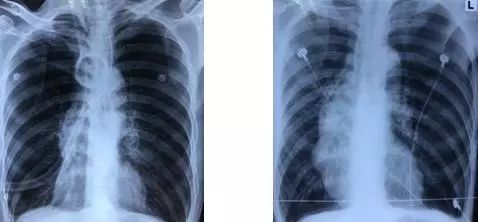

术后3天复查胸部平片(图6)提示:右肺容积较前减少,纵隔右移,膈肌穹顶较前提高。

图6 ELVR术前(左)与术后3天(右)床边胸部平片